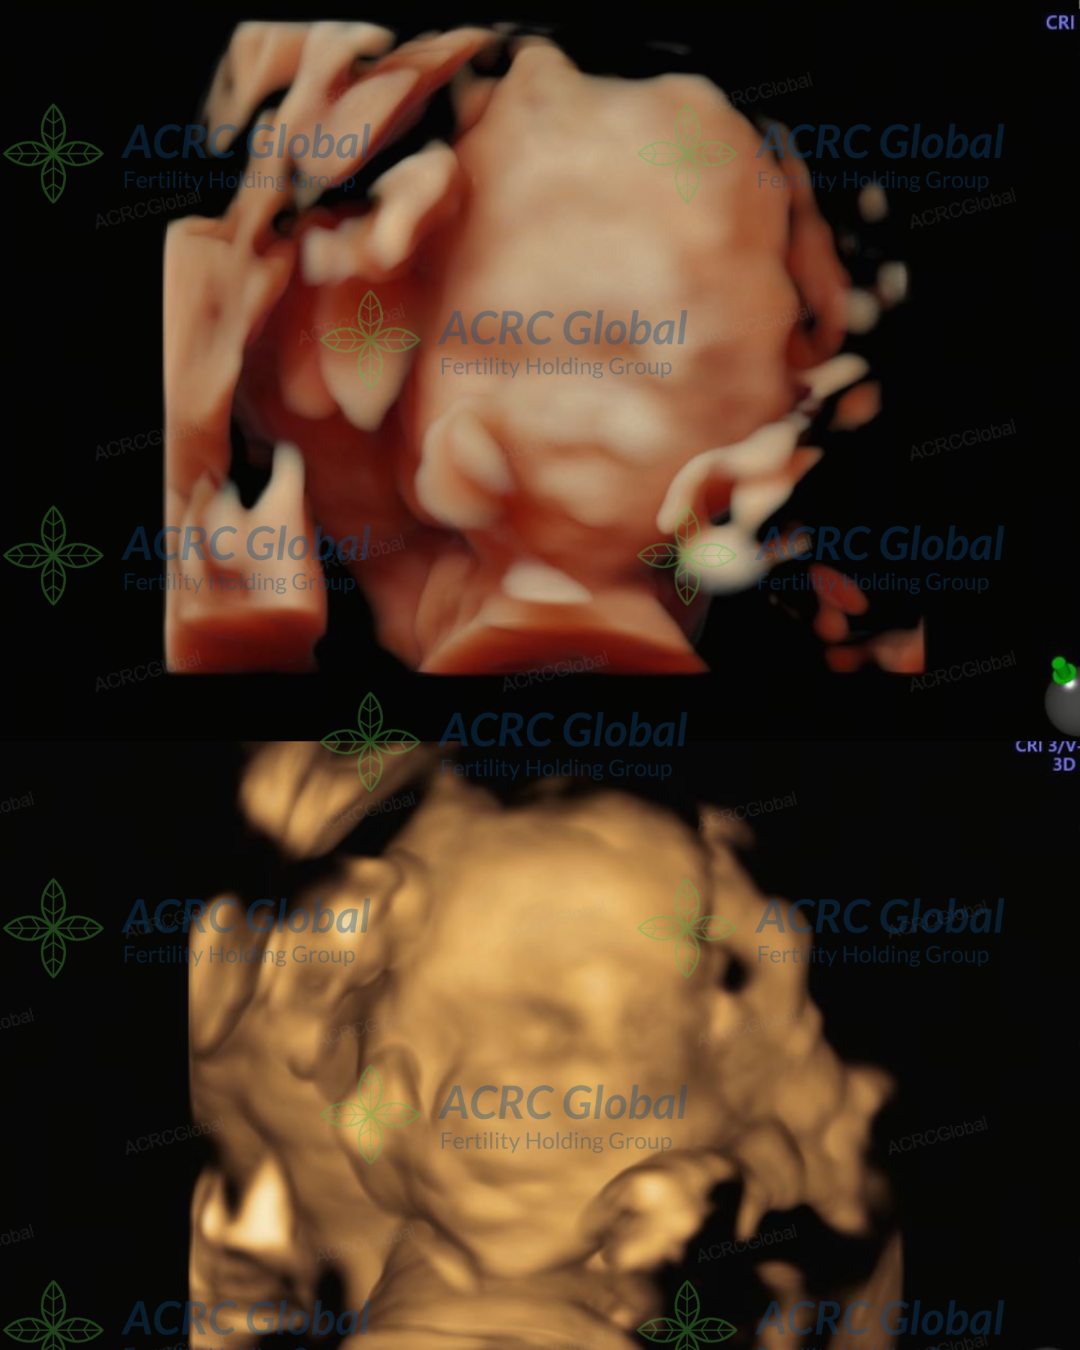

妊娠の節目:代理母Jの20週精密超音波検査が無事完了

ACRCカリフォルニアチームより嬉しいご報告です。料理やアウトドアを愛するカリフォルニア出身の代理母Jが、胎児の詳細な発育状況を確認する20週の精密超音波検査(アナトミースキャン)を無事に通過しました。この重要な検査により、赤ちゃんの発育が順調であり、すべての指標において健康に成長していることが確認されました。